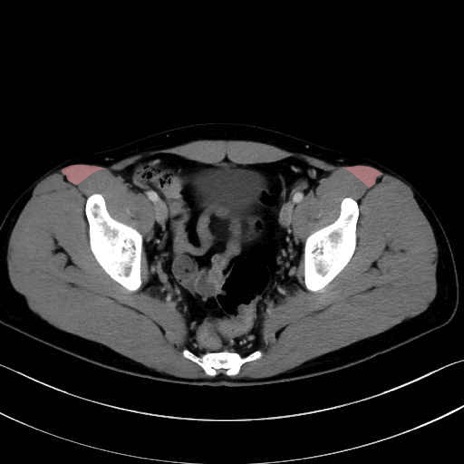

大腿筋膜張筋 (Tensor fasciae latae)

4. 深層外旋六筋(股関節の深部)

梨状筋 (Piriformis)